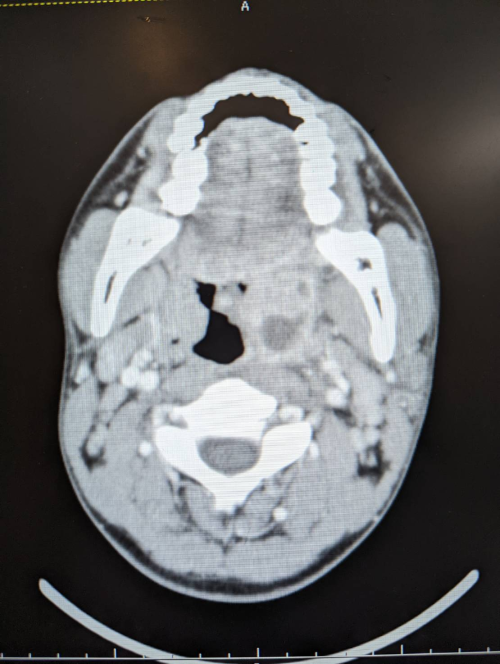

図3 頸部造影CT

造影CTで左の扁桃周囲に膿瘍を認め、扁桃周囲膿瘍と診断しました。続いて治療はどうしましょうか。